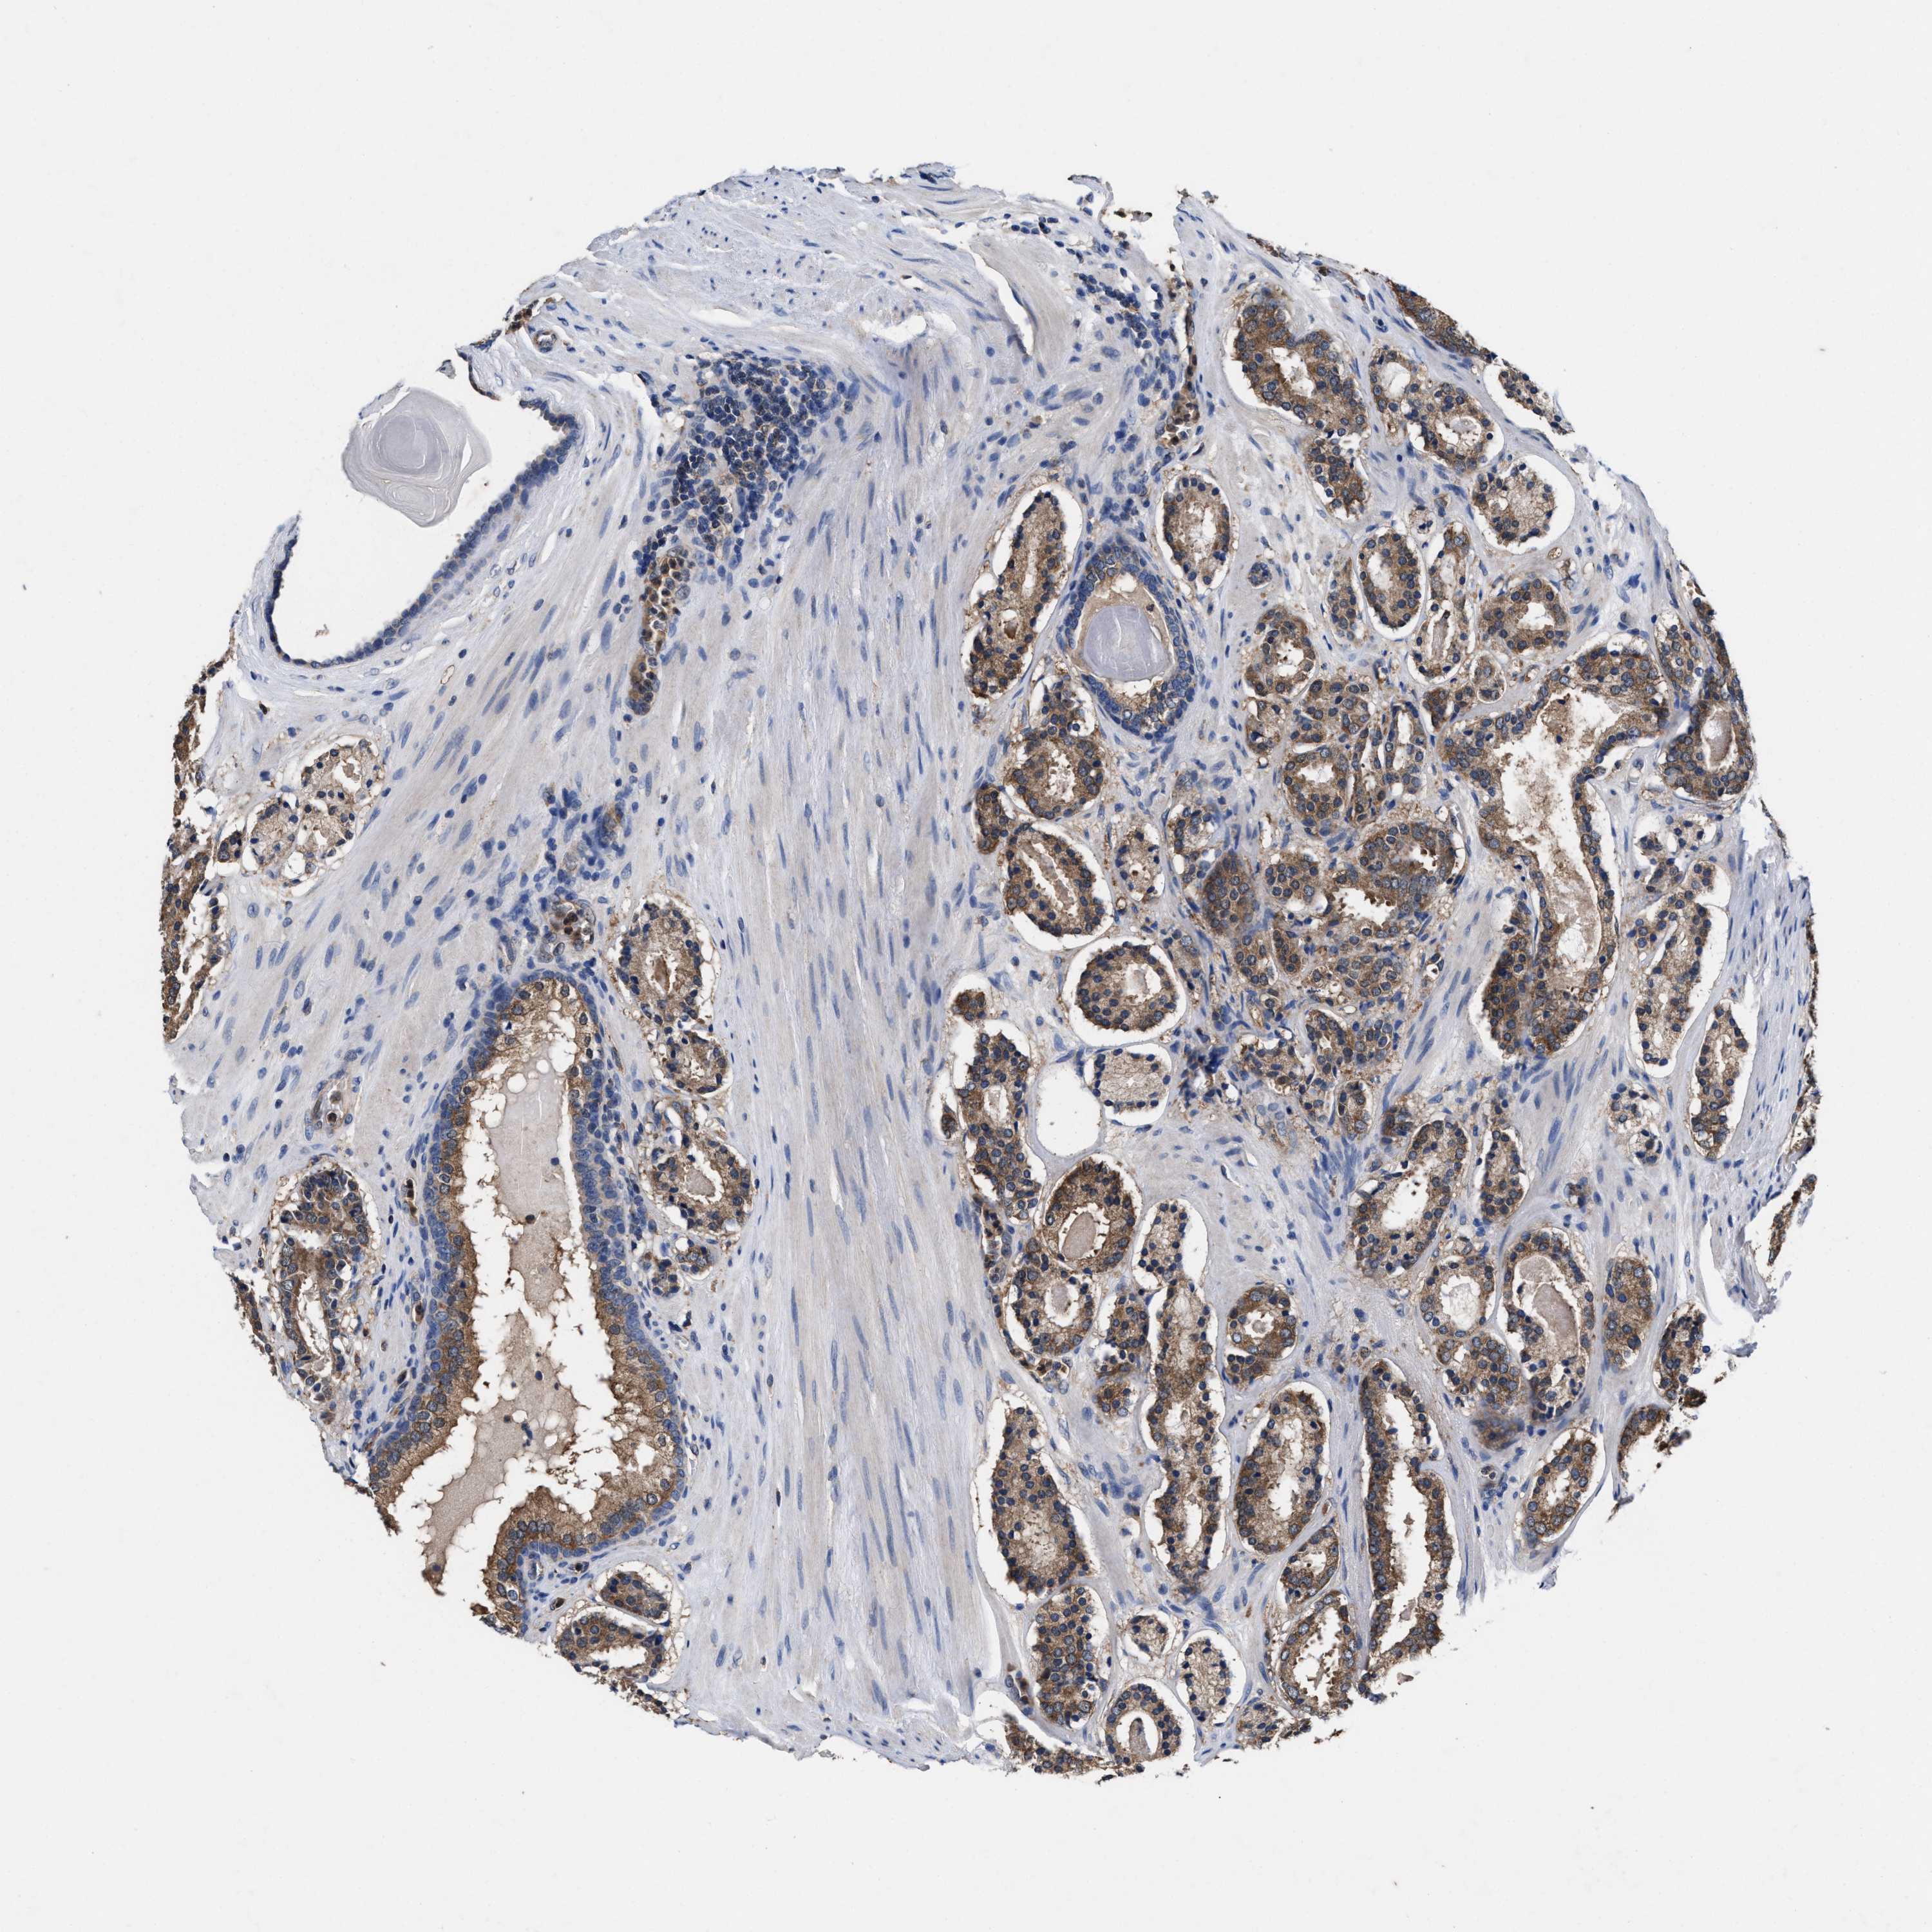

PROSTATE CANCER - Protein expressioni

A mouse-over function shows sample information and annotation data. Click on an image to view it in a full screen mode. Samples can be filtered based on level of antibody staining by selecting one or several of the following categories: high, medium, low and not detected. The assay and annotation is described here.

Note that samples used for immunohistochemistry by the Human Protein Atlas do not correspond to samples in the TCGA dataset.

Antibody stainingi

Antibody staining in the annotated cell types in the current human tissue is reported as not detected, low, medium, or high, based on conventional immunohistochemistry profiling in selected tissues. This score is based on the combination of the staining intensity and fraction of stained cells.

Each image is clickable and will lead to virtual microscopy that enables deeper exploration of all samples and also displays staining intensity scores, fraction scores and subcellular localization as well as patient and tissue information for each sample.

HPA022434

HPA022953

HPA022959

HPA028758

CAB007783

Adenocarcinoma, High grade

Adenocarcinoma, Low grade